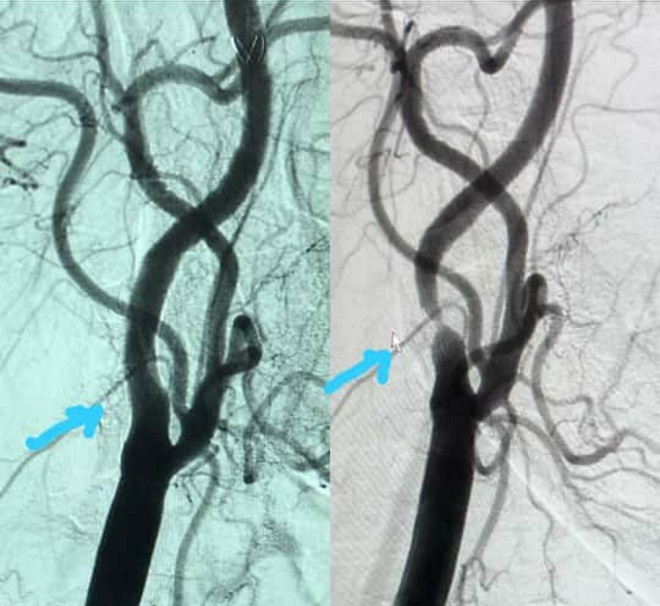

However, Dr. Allam Alkowatli, MD, Consultant Interventional Cardiologist and Vascular Interventionalist and the Chief of Cardiovascular Medicine at Emirates Hospital – Jumeirah after evaluation of this patient, recommended a minimally invasive procedure, that requires the placement of a special stent in her carotid artery to remove the plaque and lower the risk of imminent stroke in the near future but without performing any major surgery.

The stents selected for such procedures are USA-FDA approved and inserted under fluoroscopy through a tiny opening in the upper thigh using a special tube and filter wire. This helped to open up the artery and therefore decreasing the chance of it narrowing again.

The procedure was performed at the Interventional Cardiology & Vascular Catheterization Laboratory Suite of Emirates Hospital Jumeirah and lasted less than 30 minutes. It was greatly successful in eliminating the blockage without any complications. The patient was discharged to home in less than 24 hours.

Carotid stenting is a minimally invasive vascular procedure supported by major US and European Trials and is highly recommended by international experts due to its minimally invasive nature and high success rate when performed by expert. There is no major wound or scar involved with this procedure as only a very small nick in the skin and blood vessel in the groin is performed that heals in 5 days.